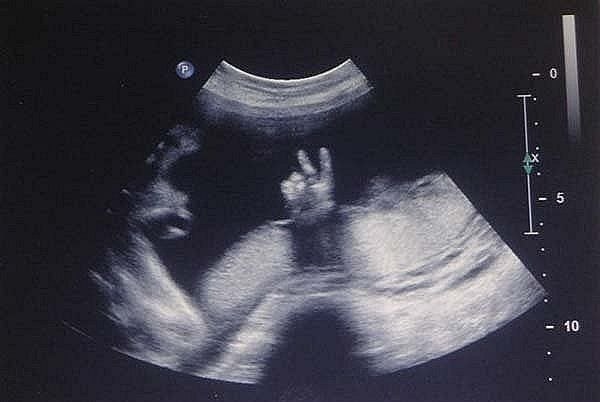

Фотоконкурс! "Самое прикольное фото с УЗИ"!

Добрый день дорогие девочки! Предлагаю вам не много отвлечься и поучаствовать в фотоконкурсе "Самое Прикольное фото с УЗИ"!!!

4. Принимаются любые фото с вашего УЗИ и 2D, и 3D, и 4D.